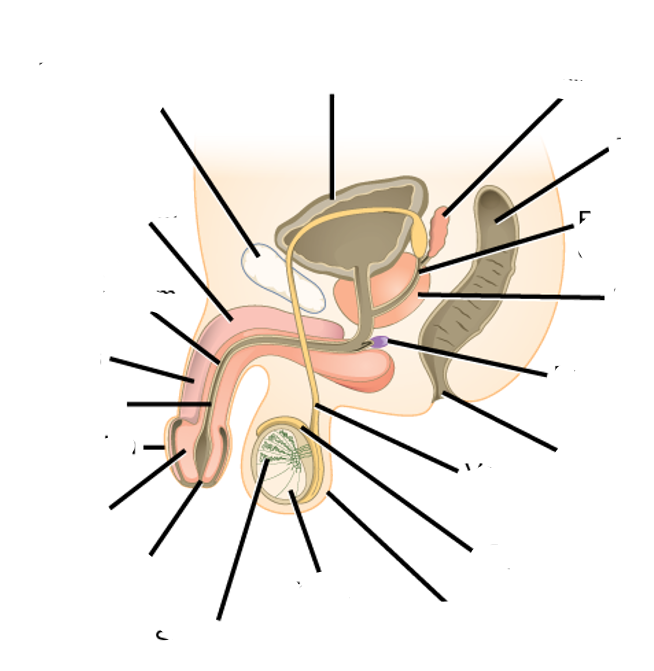

what do you see